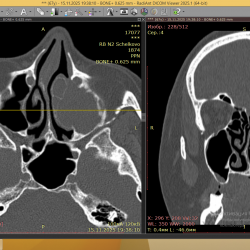

Острый верхнечелюстной синусит, КТ после ~1 месяца лечения(курс антибиотиков + сосудосуживающие(неделя), а также топические интраназальные стероиды + промывания солевым раствором +...